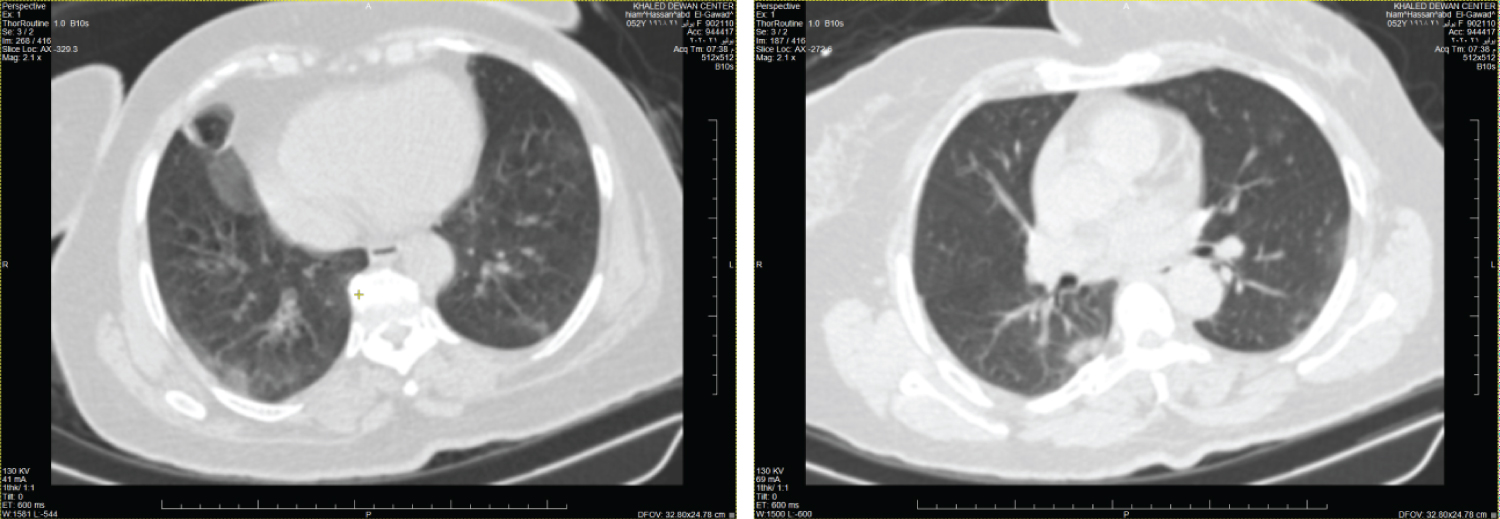

Figure 1: Female patient aged 51-years-old had negative initial reverse transcription-polymerase chain reaction results. Axial and coronal CT chest cuts shows diffuse mosaic lung attenuation with bilateral basal fine at electatic bands likely of cardiac causes (CORADS 1). View Figure 1

Figure 2: Male patient aged 49-years-old had negative initial reverse transcription-polymerase chain reaction results. Axial CT chest cuts show bilateral decreased both lung attenuation with increased both lung volumes denoting hyperinflation associated with bilateral upper lobe fine centrilobular ground glass nodular infiltration suggestive of smoking related bronchiolitis (respiratory bronchiolitis) (CORADS 1). View Figure 2